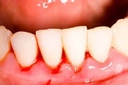

Diş ekimi, kaybedilen dişlerin yerine yapay dişlerin yerleştirilmesi işlemidir. Bu işlem, hem estetik hem de fonksiyonel açıdan birçok avantaj sunmaktadır. Diş ekimi, günümüzde diş hekimliği alanında en yaygın kullanılan yöntemlerden biri haline gelmiştir. Bu makalede, diş ekiminin faydaları detaylı bir şekilde ele alınacaktır. Diş Ekimi Nedir?Diş ekimi, kaybedilen dişlerin yerine cerrahi bir işlemle titanyum veya benzeri malzemelerden yapılan yapay diş köklerinin yerleştirilmesini içeren bir tedavi yöntemidir. Bu işlem, diş kaybının neden olduğu estetik kaygıları gidermenin yanı sıra, çiğneme fonksiyonunu da yeniden kazandırmaktadır. Diş Ekiminin Estetik FaydalarıDiş ekimi, hastaların gülümseme estetiğini önemli ölçüde iyileştirmektedir. Aşağıdaki avantajlar estetik açıdan dikkate değerdir:

Diş Ekiminin Fonksiyonel FaydalarıDiş ekiminin fonksiyonel avantajları da oldukça önemlidir. Bu avantajlar şunlardır:

Diş Ekiminin Sağlığa FaydalarıDiş ekimi, sadece estetik ve fonksiyonel avantajlar sunmakla kalmaz, aynı zamanda sağlık açısından da faydalar sağlar: